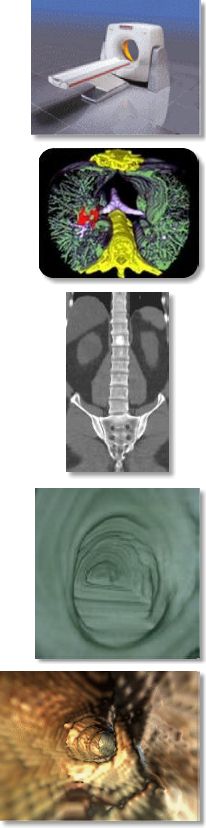

Multi-slice (or multi-detector) CT is a helical or spiral CT scanner with multiple detectors that are capable of scanning several slices simultaneously while in the helical mode, thus significantly increasing scan speed and resolution. The number of detectors ranges from 2 to 16 in the industry depending on the type and price of the scanner, but they all essentially accomplish the same tasks. AIC has a dual-detector MSCT.What are some applications?

For the past 2½ years, the MSCT at AIC has been performing the following specialized CT procedures not possible by conventional CT scanners or even most regular non-MSCT spiral CT scanners:

- Fast ultra-high-resolution (0.5 mm) scan of the bones for 4D isotropic reconstruction.

- 3D and 4D-CT Angiography (CTA): aorta, pulmonary, carotids, brain, runoff.

- Coronary artery calcification scoring (excellent non-invasive screening test).

- Whole-body screening scan (“ScanHealth”)

- Virtual colonoscopy, bronchoscopy, and endovascular angioscopy

- Dental Scan

- Fast high-resolution (2 to 5 mm) routine imaging of the neck and body.

- Fast high-res (0.5-1 mm) imaging of the IAC’s/Temporal bones.

- Advanced 4D workstation allowing exquisite multiplanar & 4D reformations.

ScanHealth Program

AIC has been offering for some time a screening program called ScanHealth, which includes a screening helical CT of the torso, CT coronary calcium scoring, and more optional 4D virtual colonoscopy (images on the right). Please kindly inform your patients that this program is now offered in their own backyard so they no longer have to travel hundreds of miles to get this test.For more information, please call me personally at (661) 949-8111 and/or visit our website at www.aicLancaster.com.